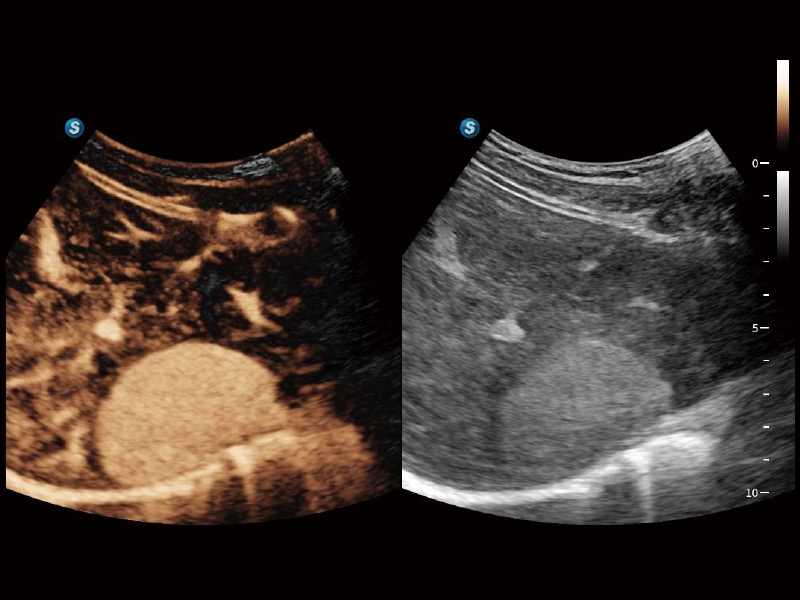

作为开立医疗全新打造的超高端旗舰超声产品,从探头抬起唤醒开启扫查到多维探头发射接收,通过先进的场成像发射、自适应聚合重建等技术,基于RF Data原始射频数据在图像生成、高端功能等方面实现突破,提供多科室综合临床解决方案。

S80 提供多样化超声成像技术,可满足不同科室的需求,在助力扫查诊断和介入治疗中发挥着重要作用。